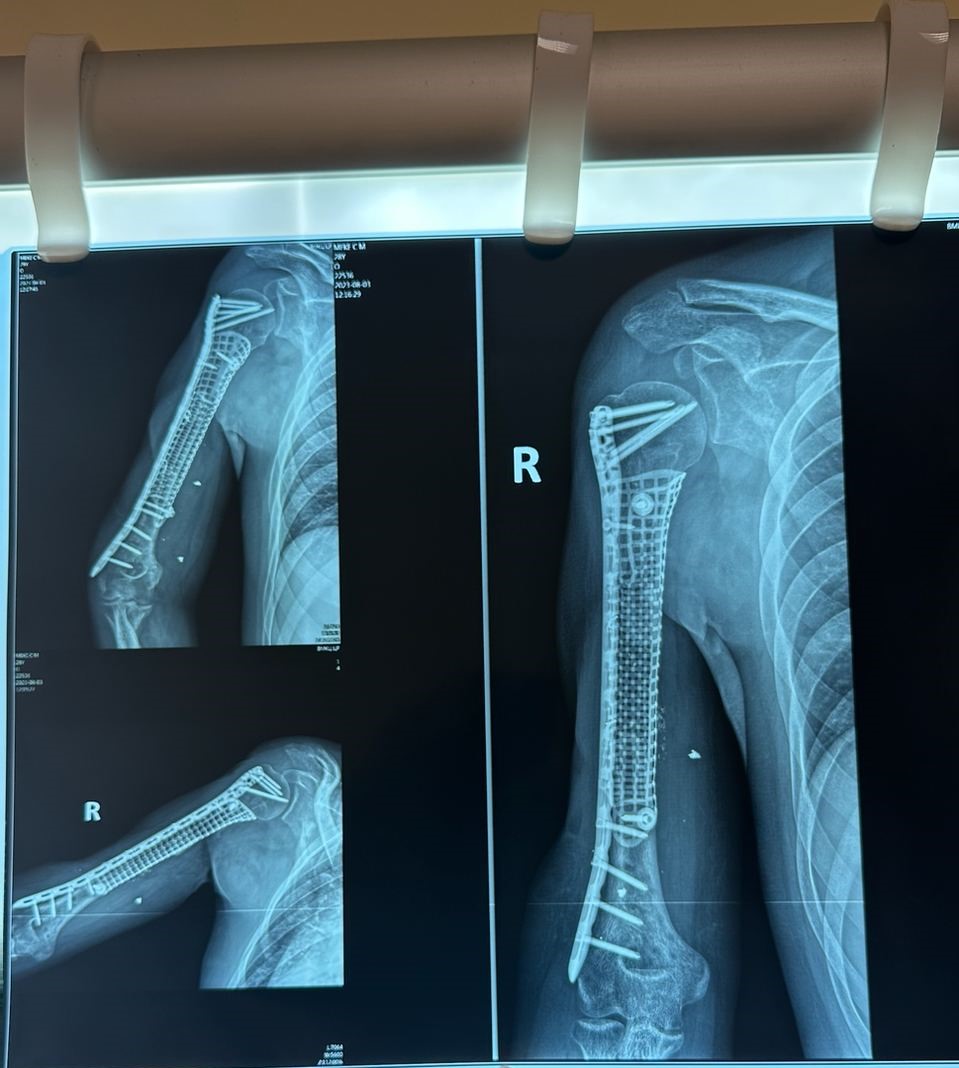

На допомогу лікарям прийшли сучасні технології. Так, було ухвалено рішення для протезування кістки використовувати індивідуальні титанові імпланти, виготовлені за допомогою 3D-технологій.

— До нас привезли пацієнта, морського піхотинця, із важким пораненням плеча: у нього була відсутня середня частина кістки, вирвано велику ділянку м’язів, але збережений суглоб. Йому пощастило, що на попередніх етапах лікування йому не ампутували руку. Ми самі, якщо чесно, спочатку вагались щодо вибору шляхів лікування. Та, врешті, ухвалили рішення рятувати кінцівку. Для нього був виготовлений 3D-титановий імплант. Але попередньо ми зі спини перемістили м’язи зі шкірою на плече. Згодом встановили імплант. За три місяці після операції воїн вже доволі непогано міг рухати рукою.

Процес виготовлення індивідуального титанового імпланта — тривалий та копіткий. Спочатку хірург створює технічне завдання, яке надсилає інженерам-волонтерам із компанії Materialise. На цьому етапі проговорюються форма, розмір конструкції, місце і тип кріплення, яким імплант буде фіксуватись. Потім інженери створюють 3D-модель, а згодом — макет. Далі лікар вносить свої зауваження, враховуючи конкретну ситуацію пацієнта. І лише потім друкується імплант із титану, адже саме цей метал найкраще інсталюється в кістку.

— Наприклад, я визначаю, що із певного боку неможливо провести гвинти, і треба дещо переробити. Таке спілкування займає певний час. А кожен протез виготовляється місяць-півтора, — зазначає Юрій Лазаренко. — Так, не в кожного пацієнта є можливість стільки чекати, і не кожен хірург надасть перевагу цій методиці, а вважатиме за потрібне користуватись звичними засобами. Проте, на мою думку, подібна технологія має право на життя, особливо якщо поранення є дуже важким. Сьогодні у нас вже є пацієнти, яким операцію провели рік тому. Вони показують доволі непогані результати.

Окрім того, військові травматологи провели унікальну для України операцію — відновили пораненому десантнику функцію плечового суглоба за рахунок індивідуального титанового імпланта.

— Цей захисник спочатку проходив лікування за кордоном, де йому надали невтішні прогнози. Ми ж вирішили поборотись за відновлення функцій пацієнта. У нього, окрім м’язів, був відсутні плечовий суглоб. Водночас, попри дуже важке поранення, збережені нерви. Зробили для нього індивідуальний 3D-протез і «під’єднали» руку до лопатки. За три тижні після операції у пораненого почала відновлюватись рухливість руки.